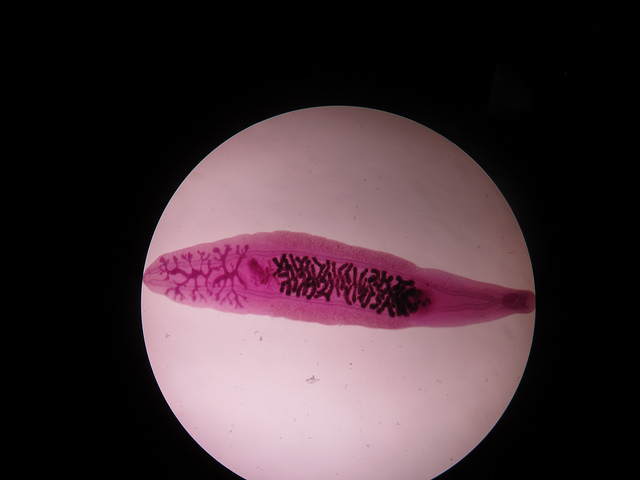

Un parasite, ou plus précisément un ver plat. Il est plus communément appelé douve. Les adultes sont petits, mesurant de 0,5 à 2 cm de long et seulement 1 à 4 mm de large. Leurs œufs, en revanche, sont des dizaines de fois plus petits qu'un millimètre (pas plus de 0,1 mm). Les trématodes infectent le foie, les voies biliaires et le pancréas.

Voici à quoi ressemble cette chose répugnante au microscope :